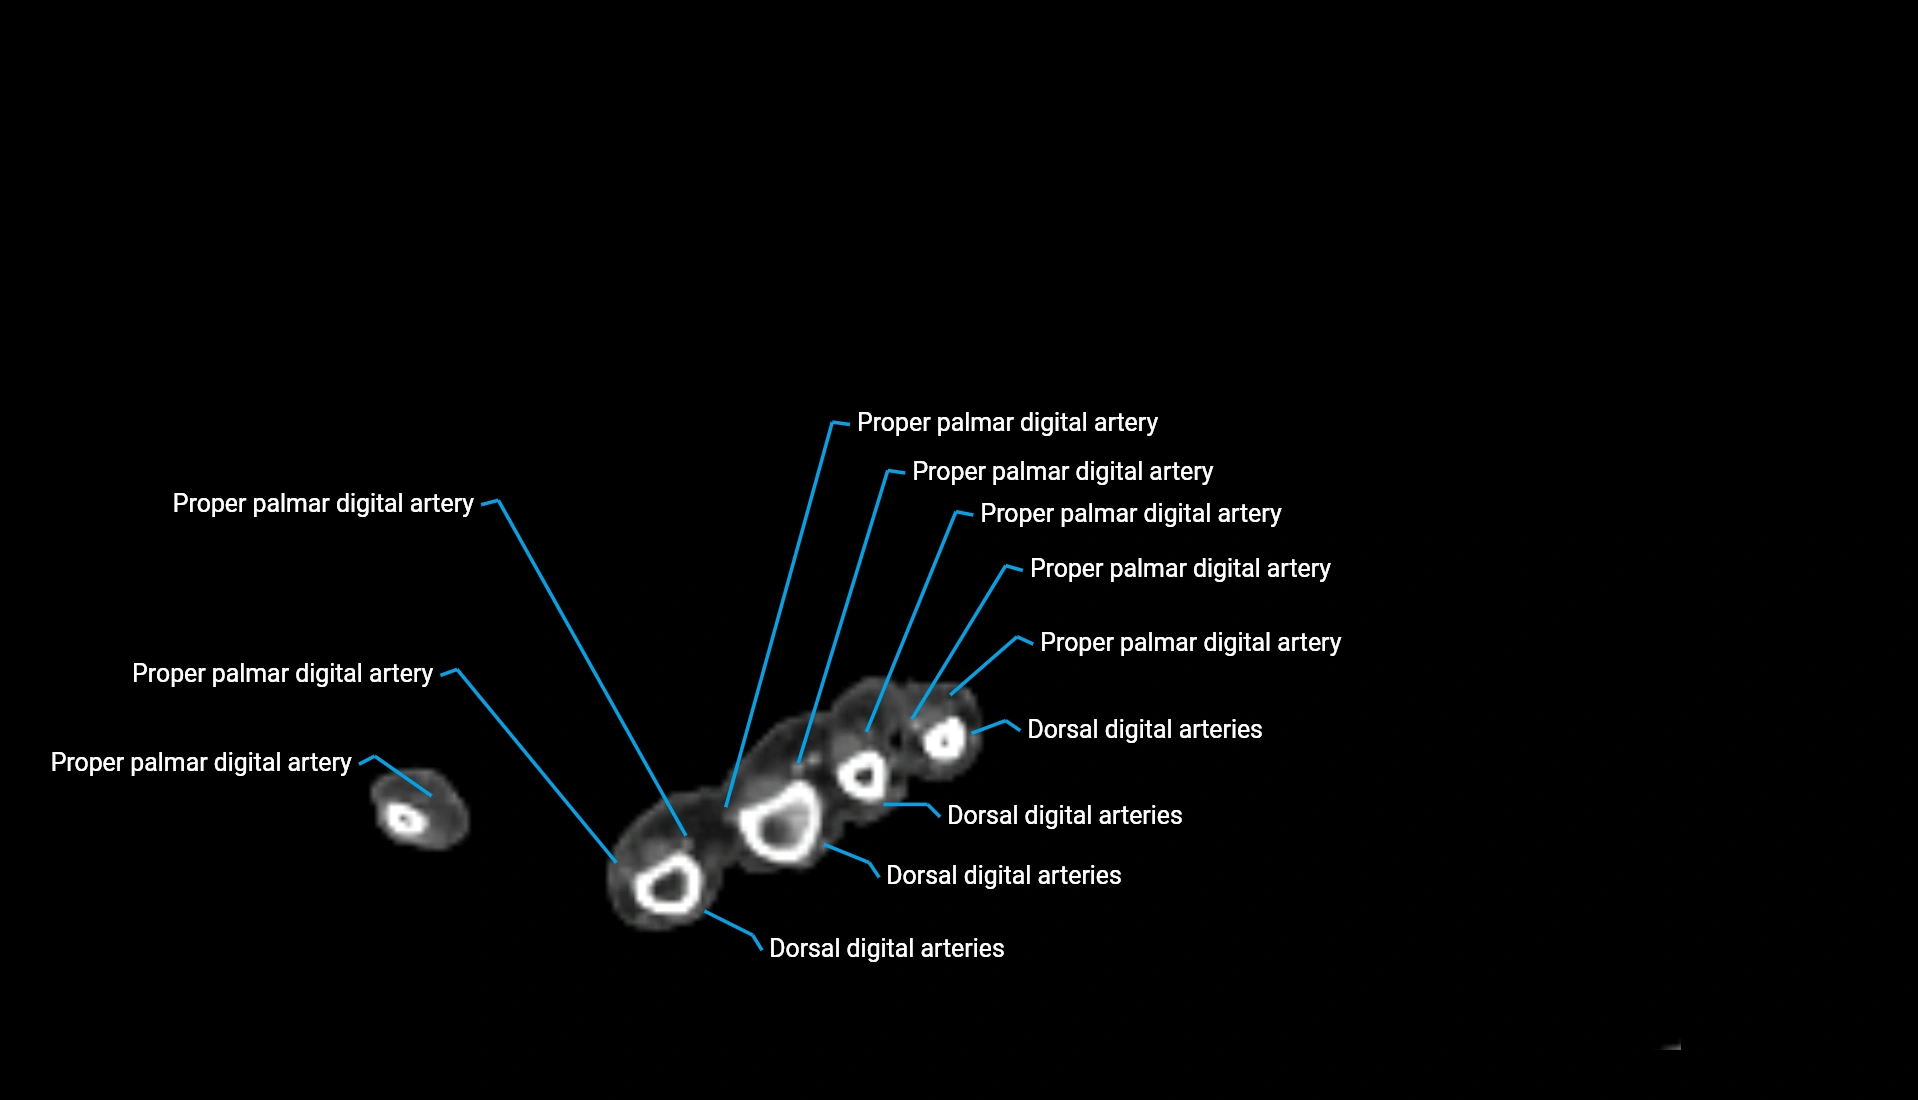

CT Appearance

Non-Contrast CT:

• Cortex: High-density, sharply defined

• Subchondral bone: Dense cancellous matrix

• Articular surface: Smooth concave contour articulating with the capitellum

• Excellent for evaluating bone integrity, alignment, and subtle fractures